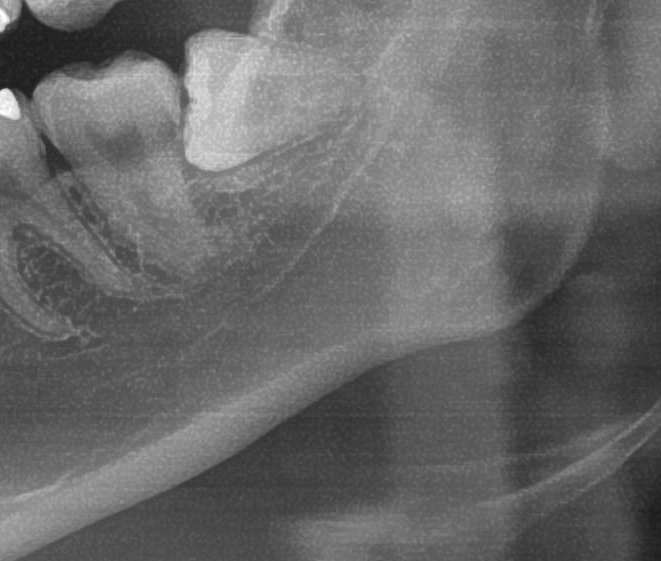

次にパノラマ写真を撮影してみると、左下の親知らずは手前の歯を押すように斜めに生えているのが確認できました。

さらに、下顎の親知らずは下歯槽神経に非常に近いところに生えている場合もあるため、CTも撮影し詳しい解析を行います。

親知らずが生えている位置が、神経に近い、あるいは神経に当たっている場合は、大きな病院に紹介する場合もあります。

親知らずの根っこは下歯槽神経から近い距離にありますが、抜歯は可能との診断でした。